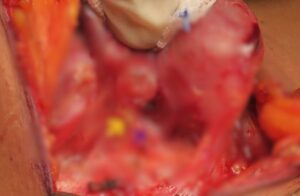

Three structures of concern during surgery are

-Recurrent laryngeal nerve which supplies muscles of vocal cords.

-External branch of superior laryngeal nerve which also supply to muscle of vocal cord.

PARA THYROID glands which maintain calcium levels in blood

(In the above picture blue arrow indicates Recurrent laryngeal nerve and yellow marks parathyroid gland)

All these nerves and parathyroid glands are dissected meticulously and preserved during surgery so that patients doesn’t have long term surgery morbidity

White arrow-Recurrent laryngeal nerve.Yellow- para thyroid gland

Wite arrow -External branch of superior laryngeal nerve(EBSLN) during total thyroidectomy for thyroid cancer

White arrow – Recurrent laryngeal nerve